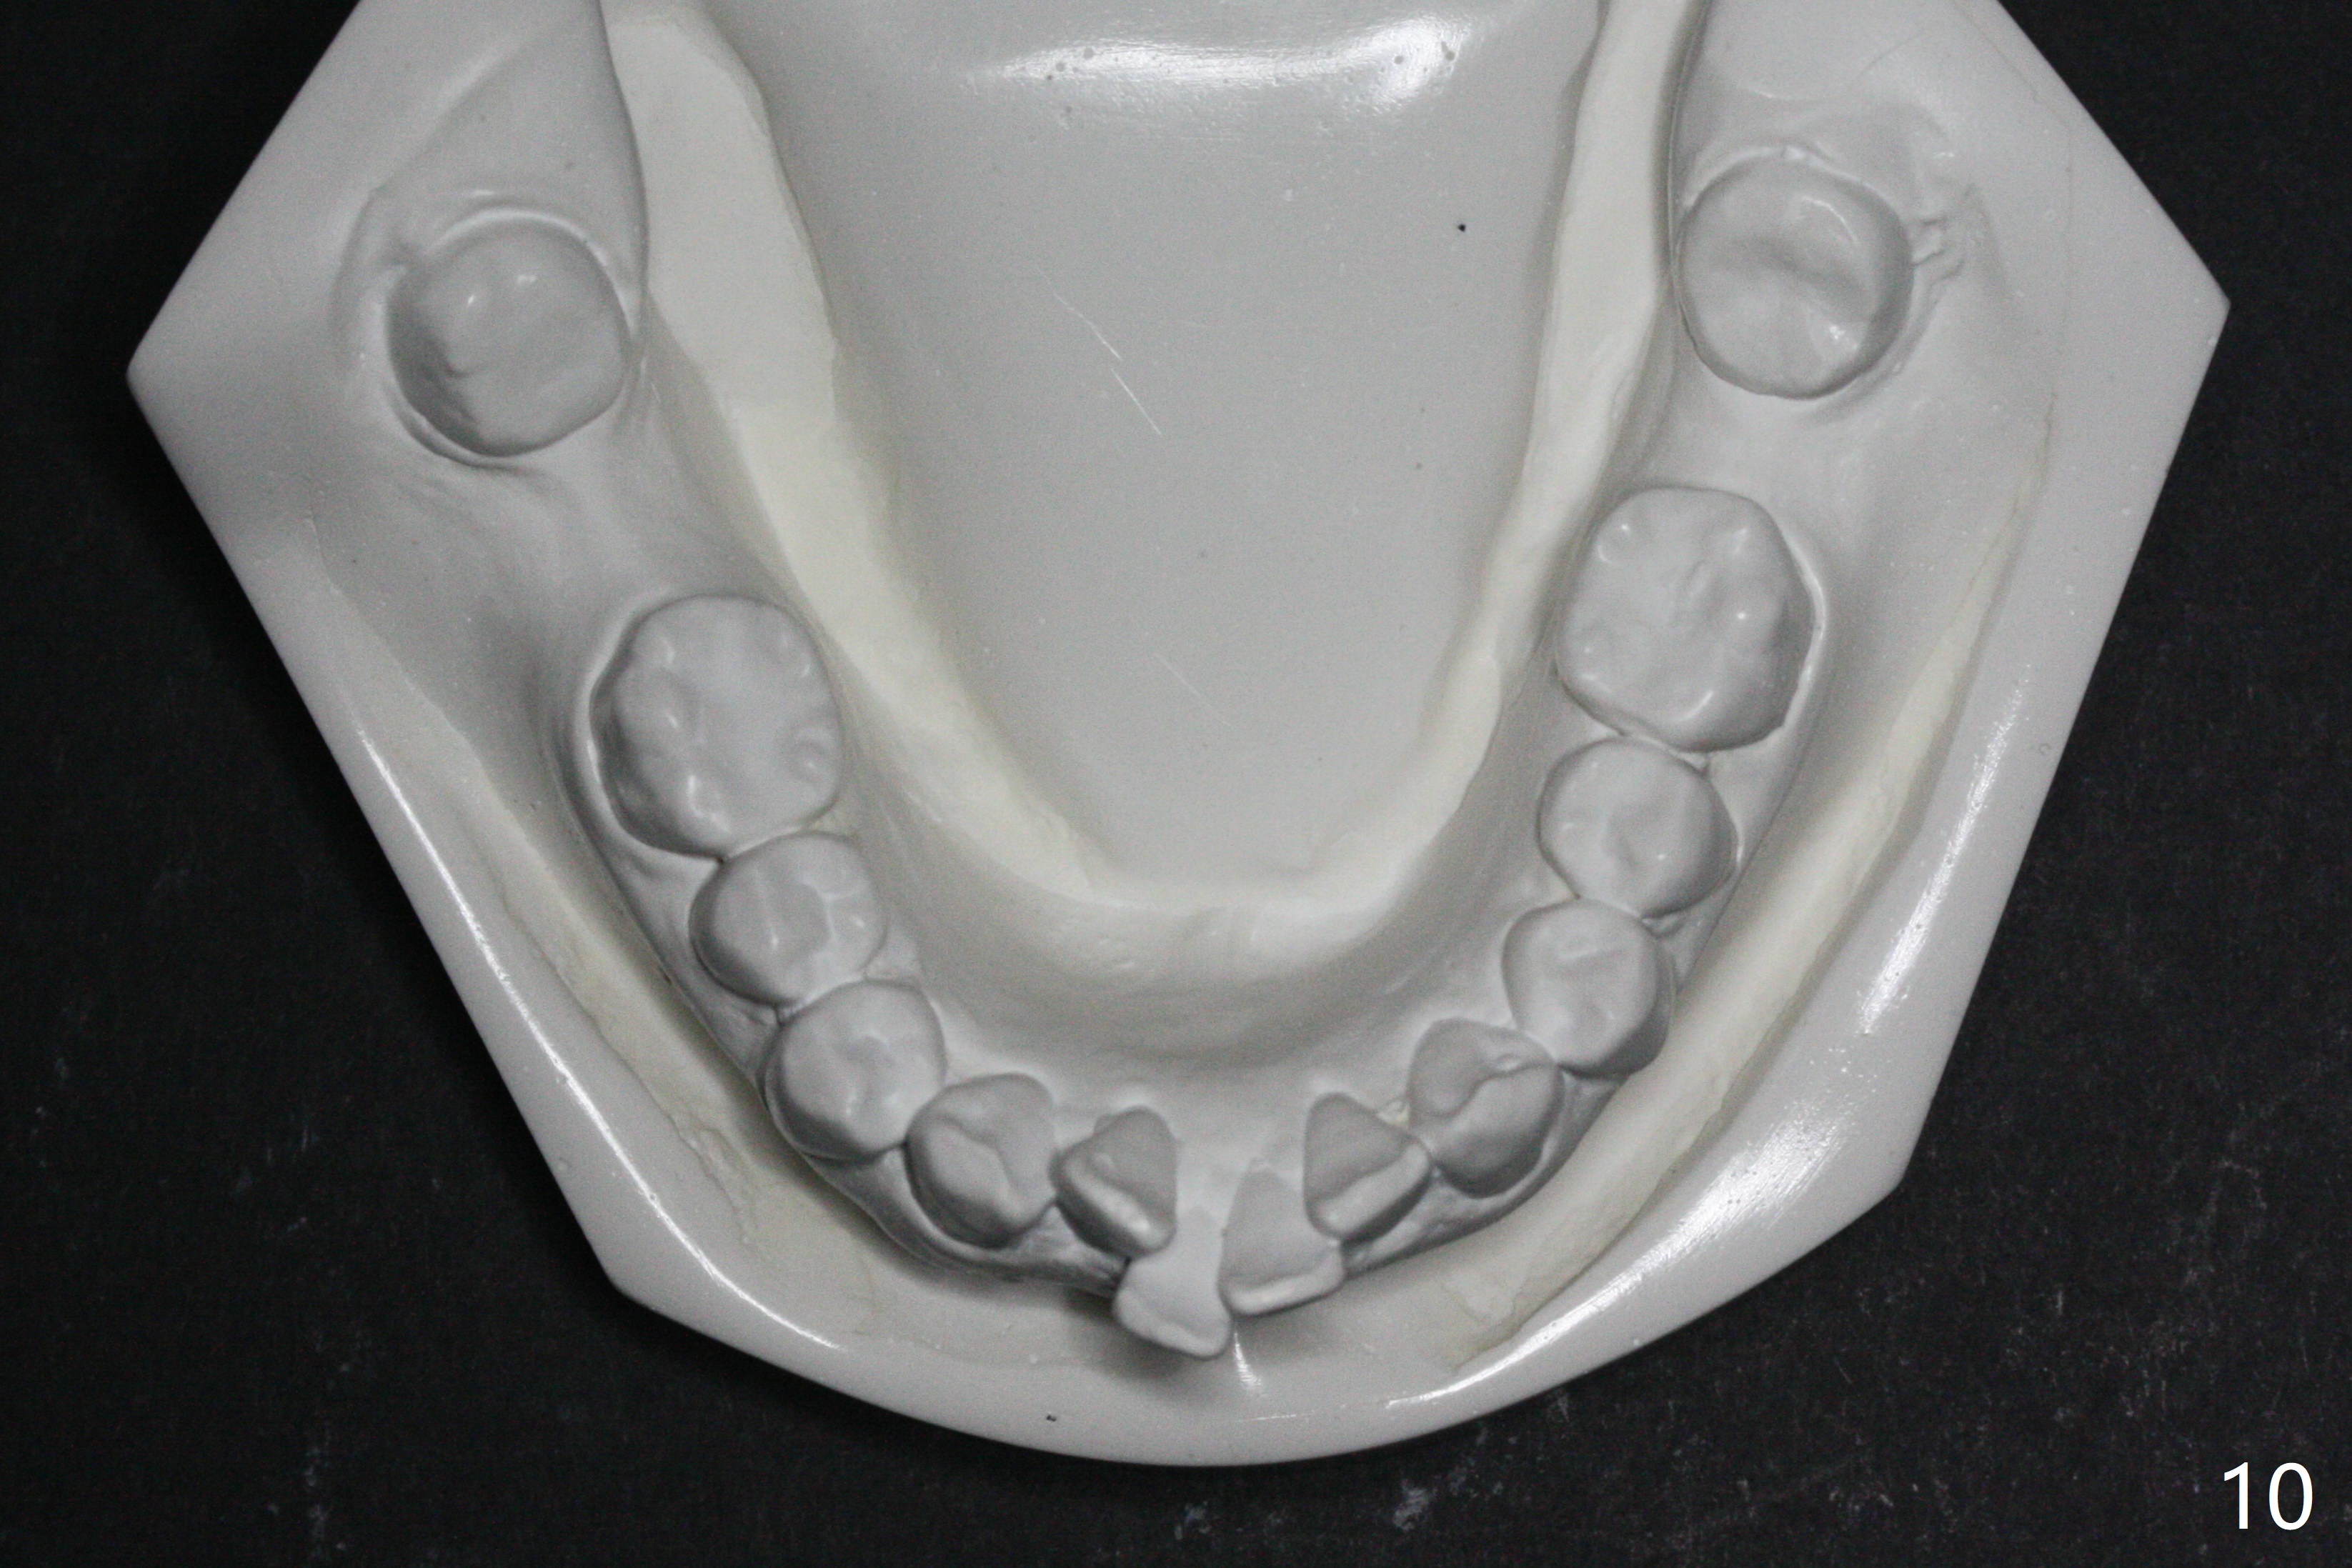

A 41-year-old woman requests ortho, bleach and replacement of 2 lower molars (L7s). The lips are protrusive (Fig.1,3), which is seemingly due to the underlying protrusive anterior teeth (Fig.4,5). Cephalometric tracing shows that SNA and SNB are both 87º (Fig.12), suggesting extraction. When the protrusive teeth are distalized, pay attention to move the upper dental midline to the right (Fig.2). BWs show subgingival calculus. SRP is required. Internal bleaching will be conducted for UL1 (Fig.7,11). Distalization is accomplished with extraction of 2 upper 1st bicuspids and using L8s as anchors so that no implants will be necessary for L7s. But the patient would rather have 2 of the lower 2nd molars for mastication. It appears that extraction of 4 bicuspids is pending (Fig.6-11). Supraeruption of U7s (Fig.6,8 arrows) will be corrected with banding.